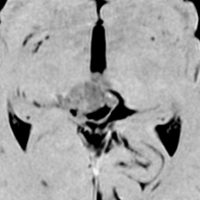

でも腫瘍増大が止められずに,発症1年後に54グレイ30分割の放射線治療を受けています。さらにその半年後くらいから再増大しましたが,スードプログレッションと考えられました。上左MRIは放射線治療前,上右MRIは放射線治療1年後です。毛様細胞性星細胞腫は放射線治療後に一過性増大(多くはのう胞性増大)することが多いです。

のう胞性拡大が止まらず,発症3年後にまた再開頭手術 (left occipital transtentorial approach) で亜全摘出しました。右は術後の画像です。初発時の最初の手術で亜全摘出あるいは全摘出 gross total removalできていればと思える例です。